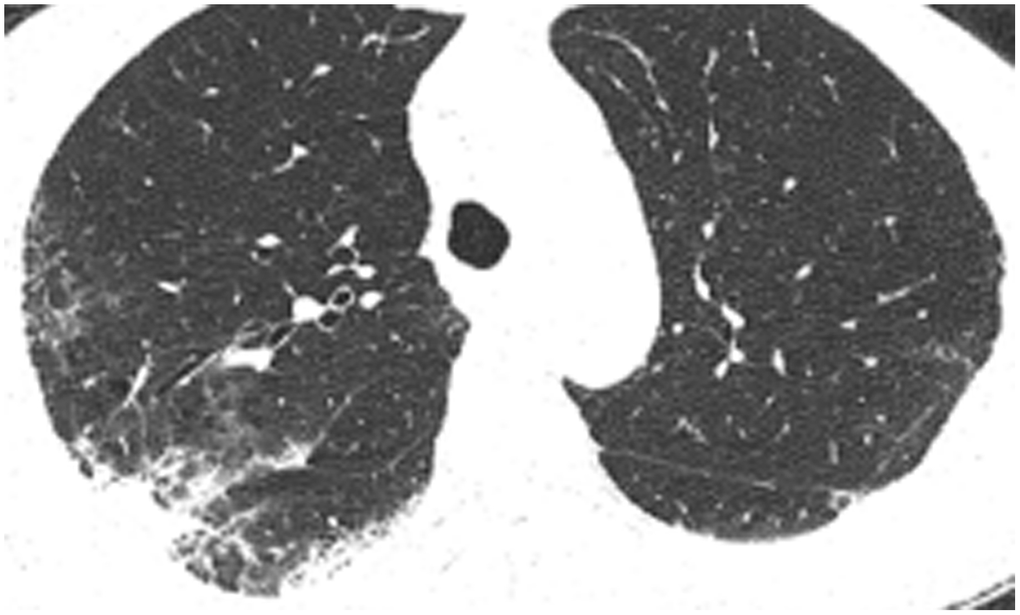

All patients were positive for the coronavirus nucleic acid test from pharyngeal swabs or blood. The blood lymphocyte counts and proportions of all patients were lower than normal (0.8×109/L) at the time of admission, and the white blood cell counts and proportions of six patients were higher than normal value (10×109/L). The blood D-dimer levels in all patients were higher than normal value (243 ng/mL) before neurological symptoms, and the C-reactive protein values in all patients were also higher than normal value (8000 μg/L). The chest CT of all patients showed flaky or frosted glass like- high-density shadow in lungs (Figures 1, 2), pleural effusion was seen in 2 cases (Figure 3), and no obvious abnormalities in 4 cases. The head CT imaging indicated that one patient had brainstem hemorrhage with ventricular cast and hydrocephalus (Figure 4), two patients had a large area of uniform low-density shadow on the frontotemporal lobe on the head CT (Figure 5), four patients had multiple flaky low-density shadow on the parietal lobe (Figure 6), one patient showed flaky low-density shadow in the pons (Figure 7), and three patients could see point-like low density shadow in basal ganglia (Figure 8).

Figure 3. Case 6, flaky or frosted glass like- high-density shadow in both lungs with pleural effusion in left lung.